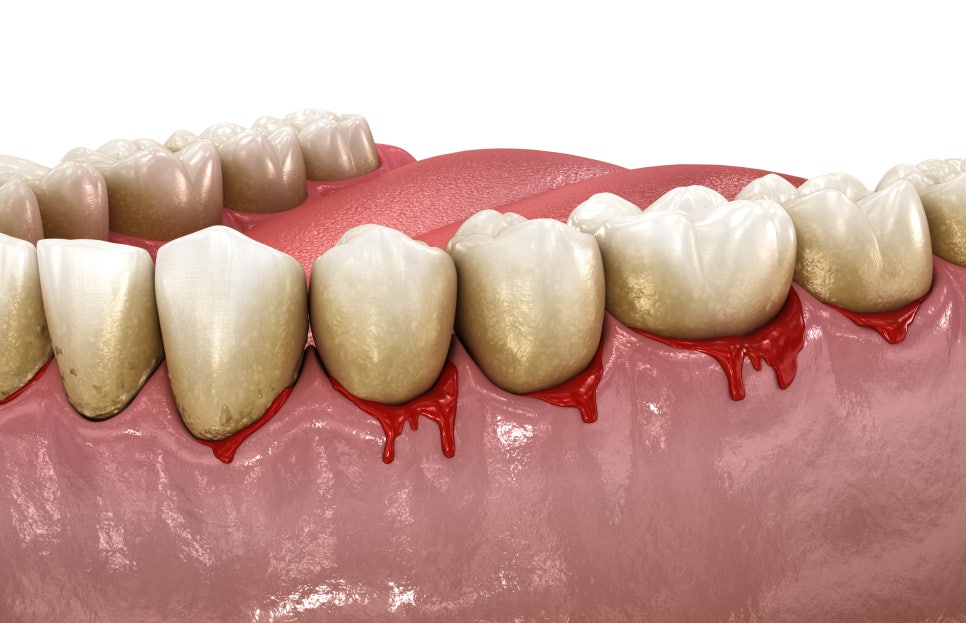

치주 질환은

우리나라 성인의 절반 이상이 겪고 있는

흔한 구강 질환으로

초기에는 증상이 미미하여

가볍게 생각하고 방치하다가

병이 깊어지고 증상이 심해지고 나면

치과를 찾는 경우가 많은데요.

치주 질환이란

치아 주위 조직인 잇몸과

치아를 지지하는

치조골과 치주 인대 등에 생기는

염증성 질환으로

크게 치은염과 치주염으로

나눌 수 있습니다.

치은염은

잇몸에만 국한되어 생긴 염증으로

이 단계에서 적절한 스케일링 받고,

올바른 칫솔질을 해준다면

회복이 가능하지만

치은염 상태에서 방치하게 된다면

치주염으로 진행이 되어

치아를 지지하는 치조골이 파괴되면서

잇몸이 내려앉게 되고,

치아와 잇몸 사이에

치주낭이라는 틈이 깊어져

심한 경우 치아가 흔들리고

빠질 수 있습니다.

치주 질환의 주된 증상

✅️ 잇몸이 붉게 변하고 붓는다.

✅️ 칫솔질을 하거나 음식물 섭취 시 피가 난다.

✅️ 치아가 흔들리거나 시린 증상이 있다.

✅️ 치아가 길어 보이는 느낌이 든다.

✅️ 양치를 꼼꼼하게 해도 입 냄새가 심해진다.